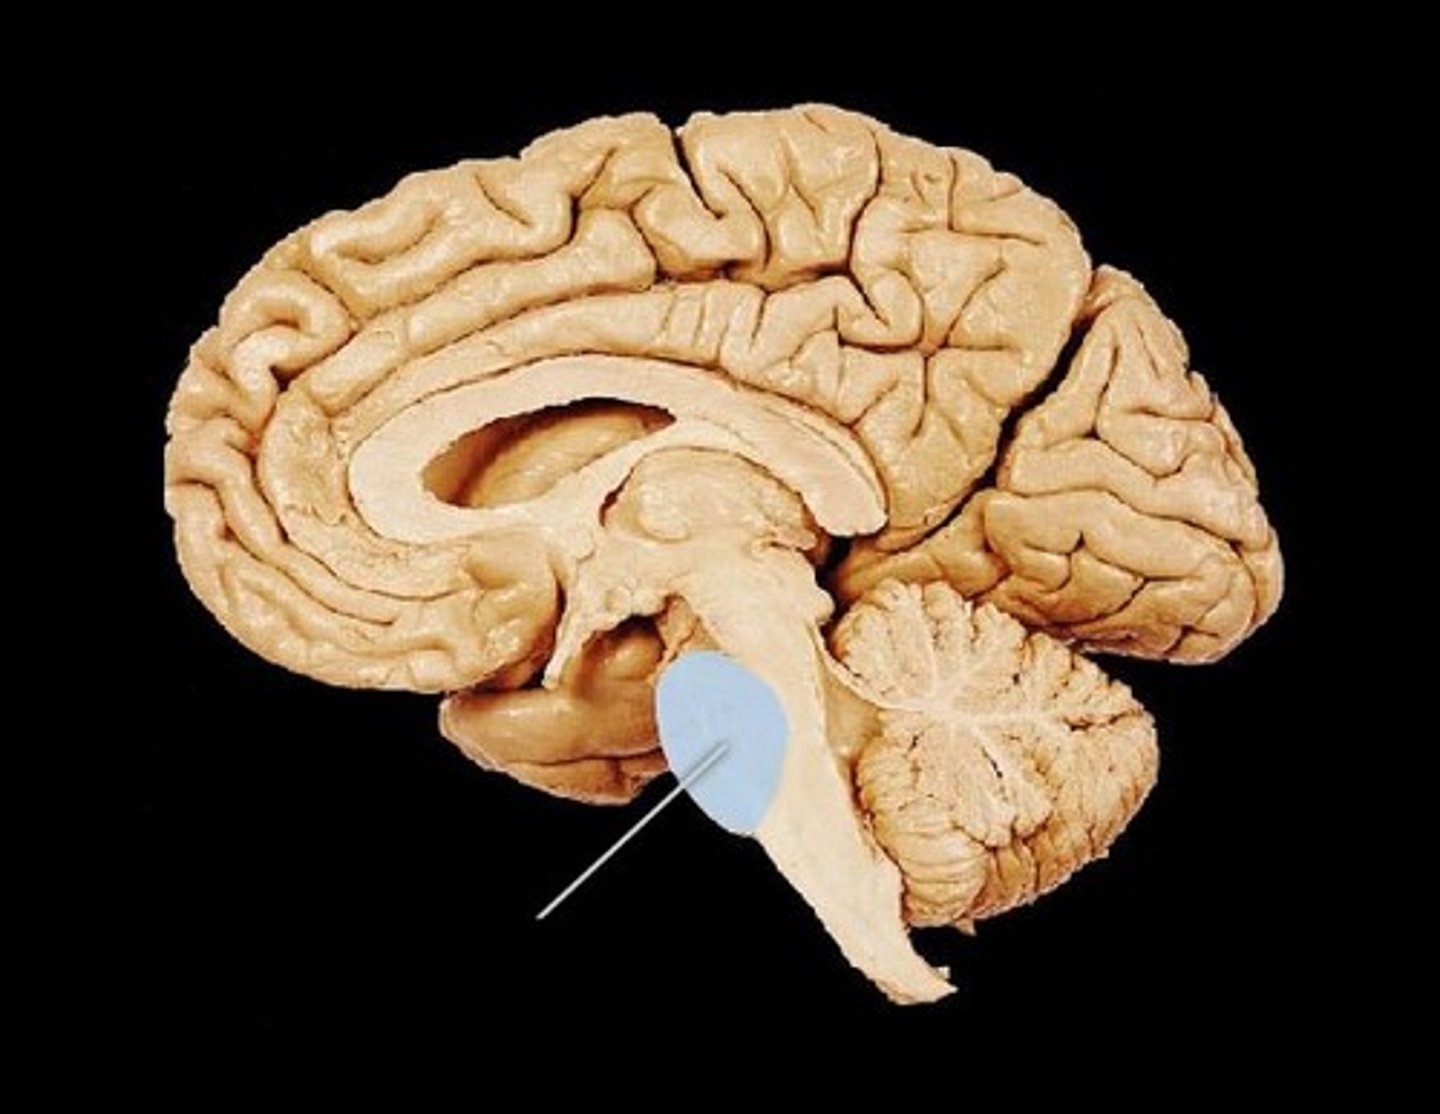

Hippocampus

small structure with two arms that wrap around the thalamus (blue in picture) - storage for conscious memories

Think of it like you have to remember how to get around a new campus